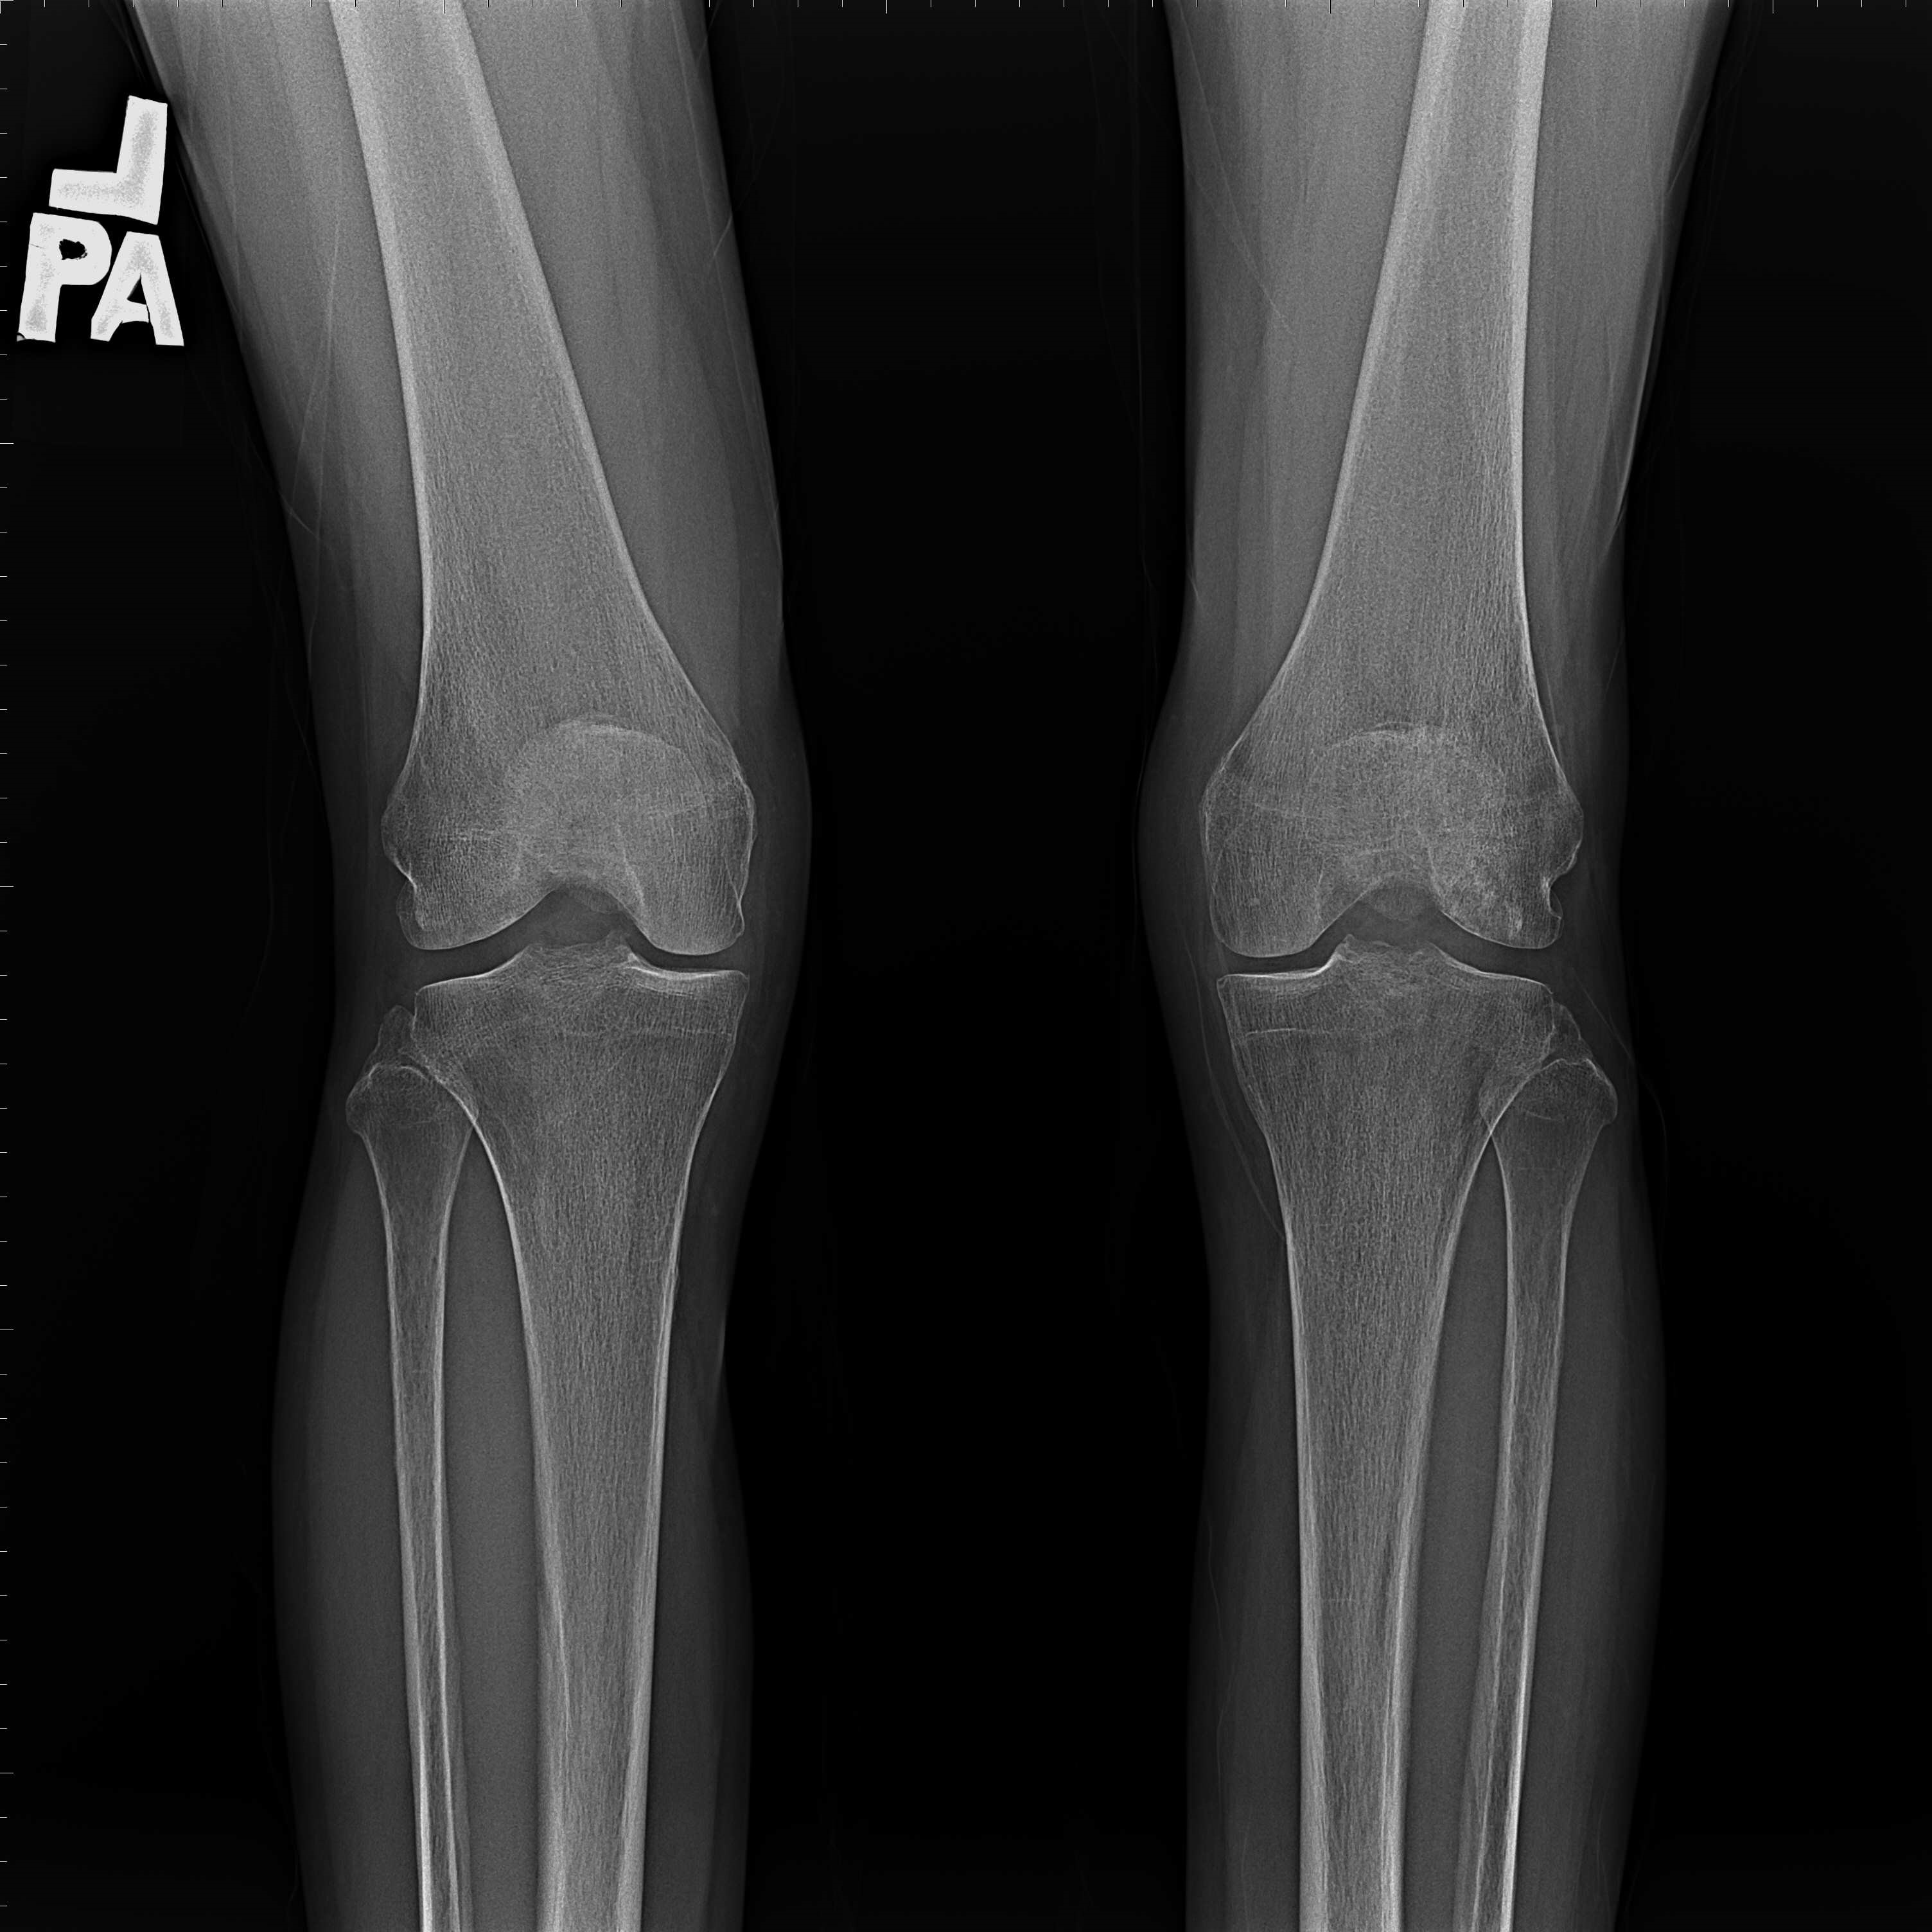

機器手臂手術 首頁 案例分享 膝關節手術 機器手臂手術 蔡女士 78歲 術前 術後 陳女士 70歲 術前 術後 術前 術後 ANGEVINE女士 73歲 術前 術後 U.S.A Mark 73歲 術前 術後 藍女士 78歲 術前 術後